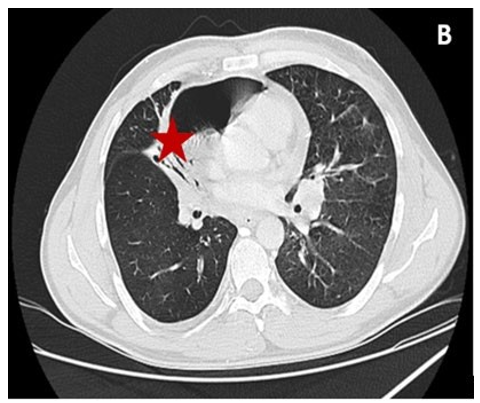

A 64 years old man with a past medical history of a lung cancer undergoing chemotherapy was admitted in the cardiology de- partment for progressive onset of dyspnea. Initially, there were no signs of cardiac tamponade. Transthoracic echocardiography showed the air gap sign, identified as the loss of signal during the systolic phase and the ‘swirling bubbles sign’ several very small bright echogenic spots in the pericardial sac. For better visual- ization, a thoracic computed tomography (CT) was performed and found a right pulmonary mass of with many small areas of gas and a pneumocardium of 24 mm of maximum thickness is shown in the Figure A and Figure B.

Figure: Cardiac Air Tamponade as a Complication of Pul- monary Mass

B: The Pulmonary Mass Fistulized in the Pericardium